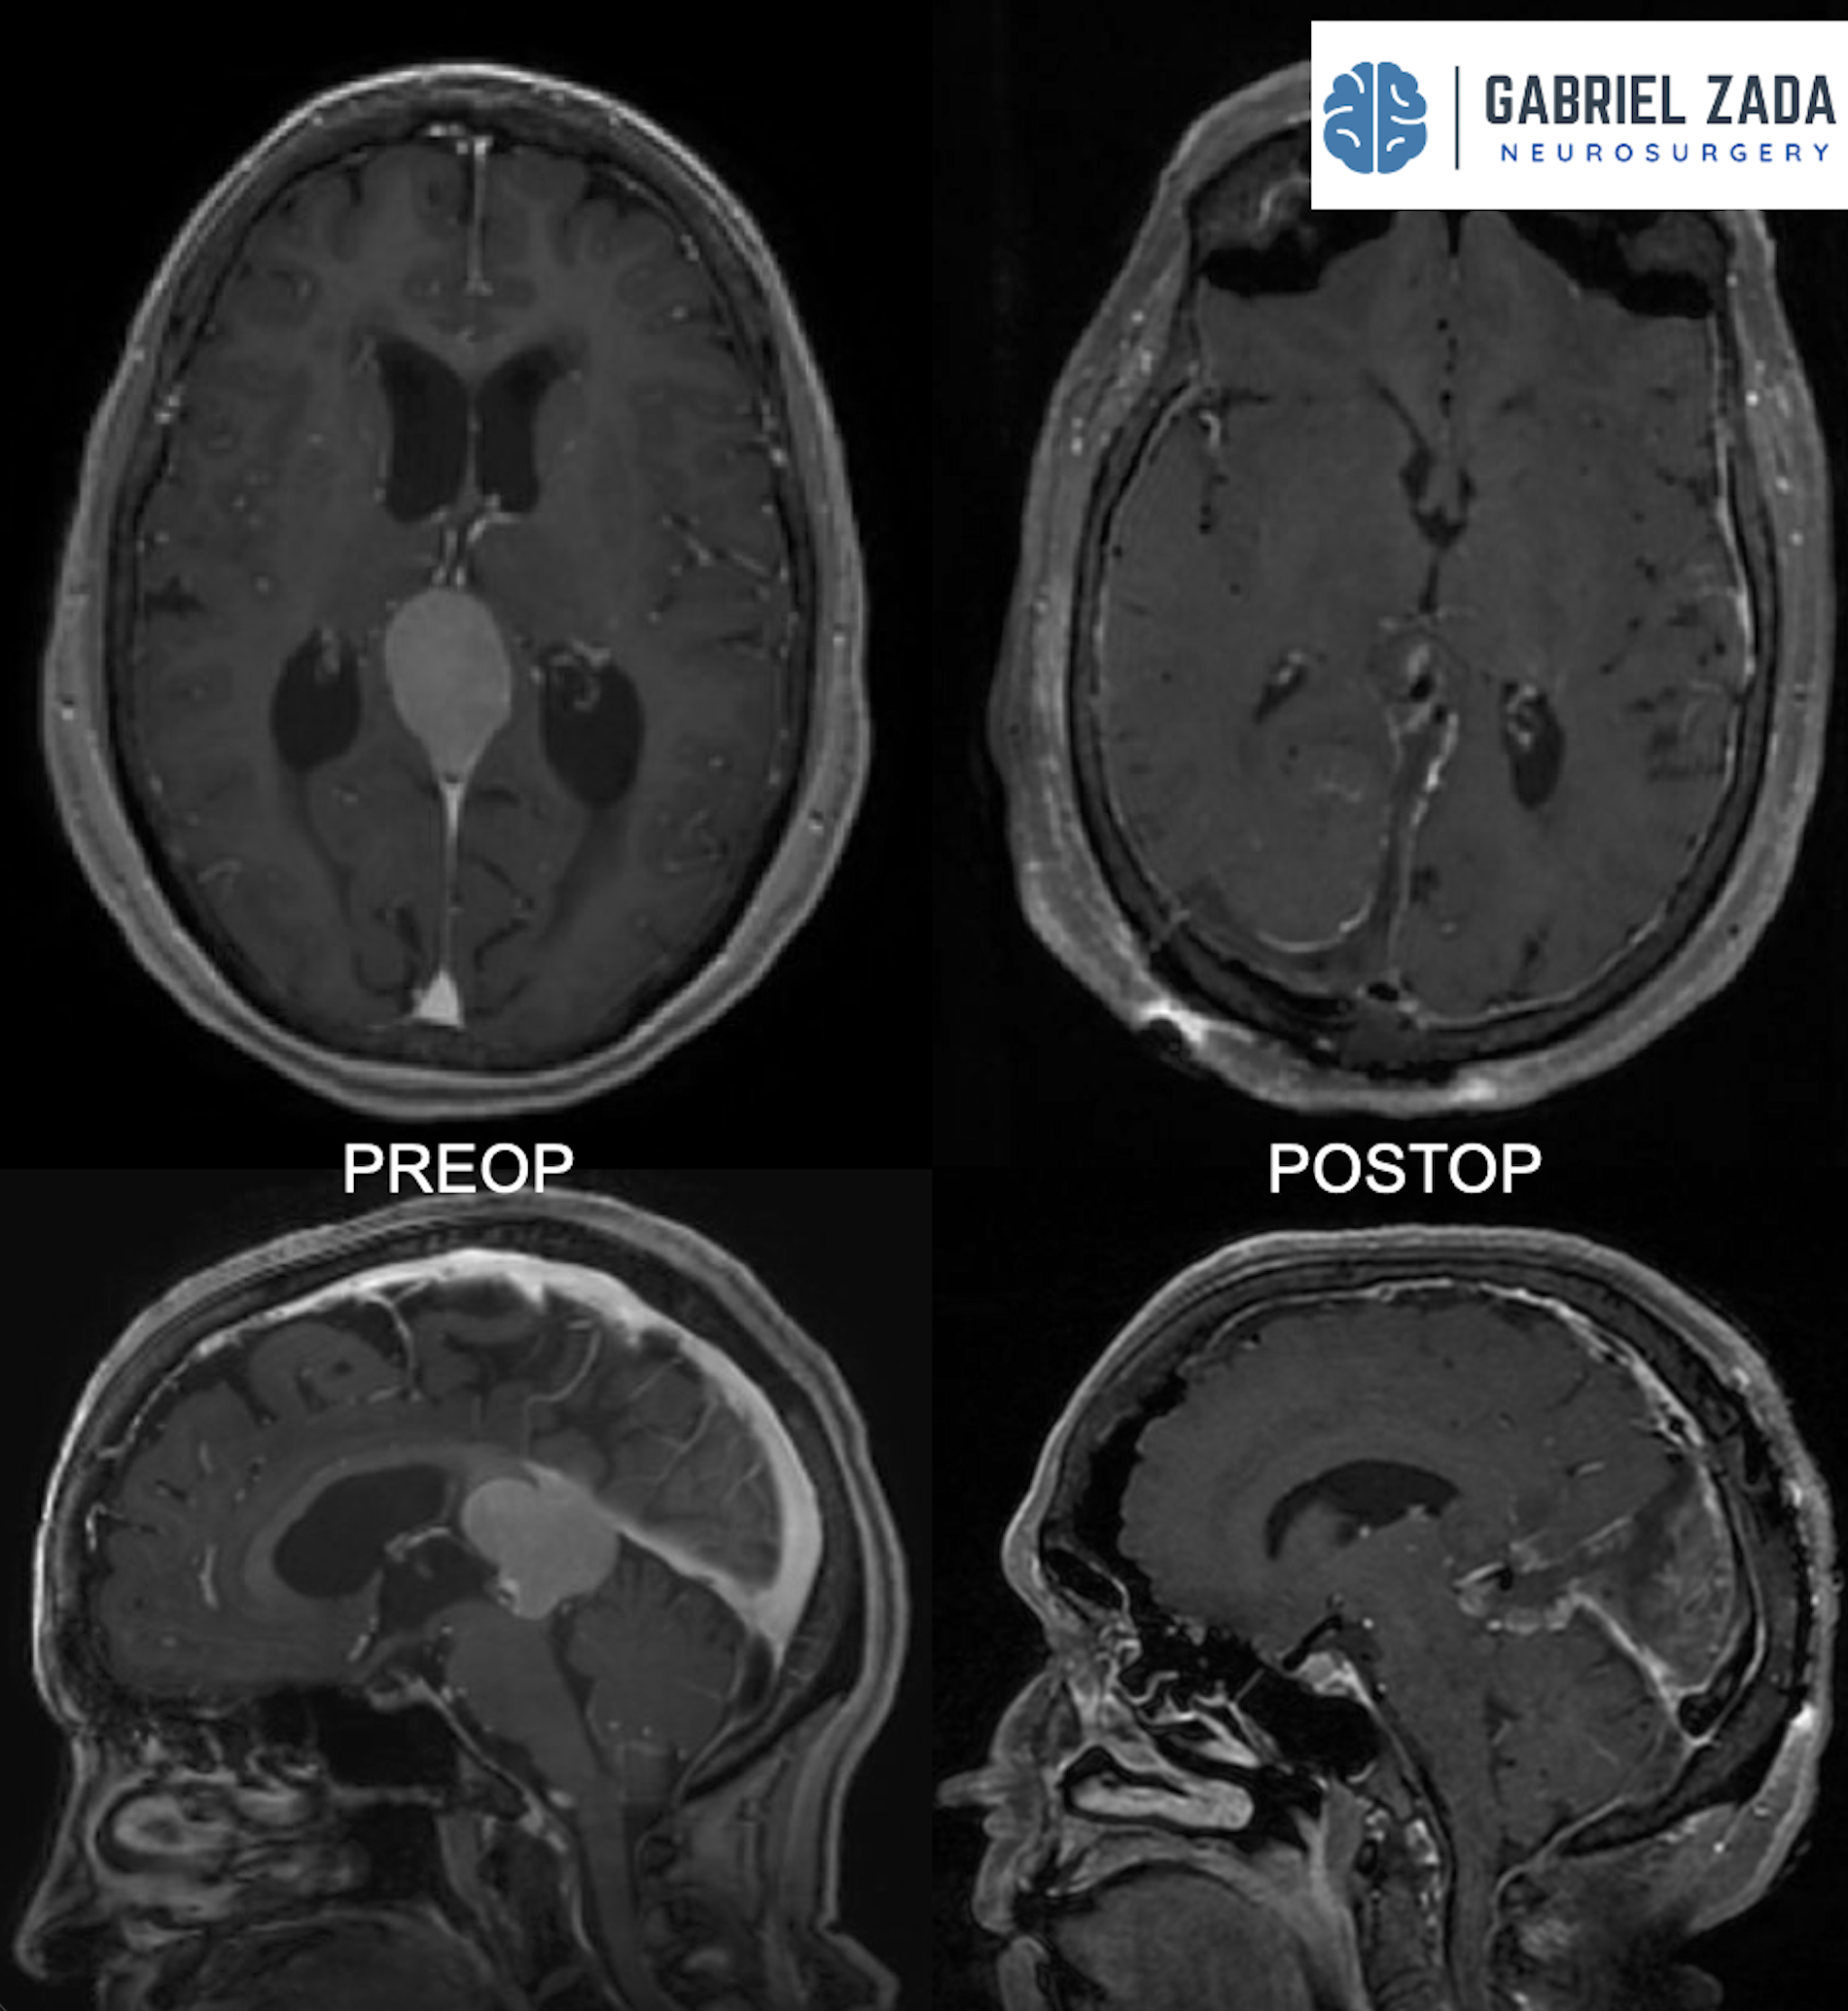

Explore this comprehensive gallery featuring pre‑ and post‑operative imaging of patients with skull‑base tumors treated by Gabriel Zada, MD, MS, FAANS, FACS. These cases highlight Dr. Zada’s expertise in advanced neurosurgical techniques and outcomes.

*Representative cases shown for educational purposes. All images de-identified. Individual results vary.